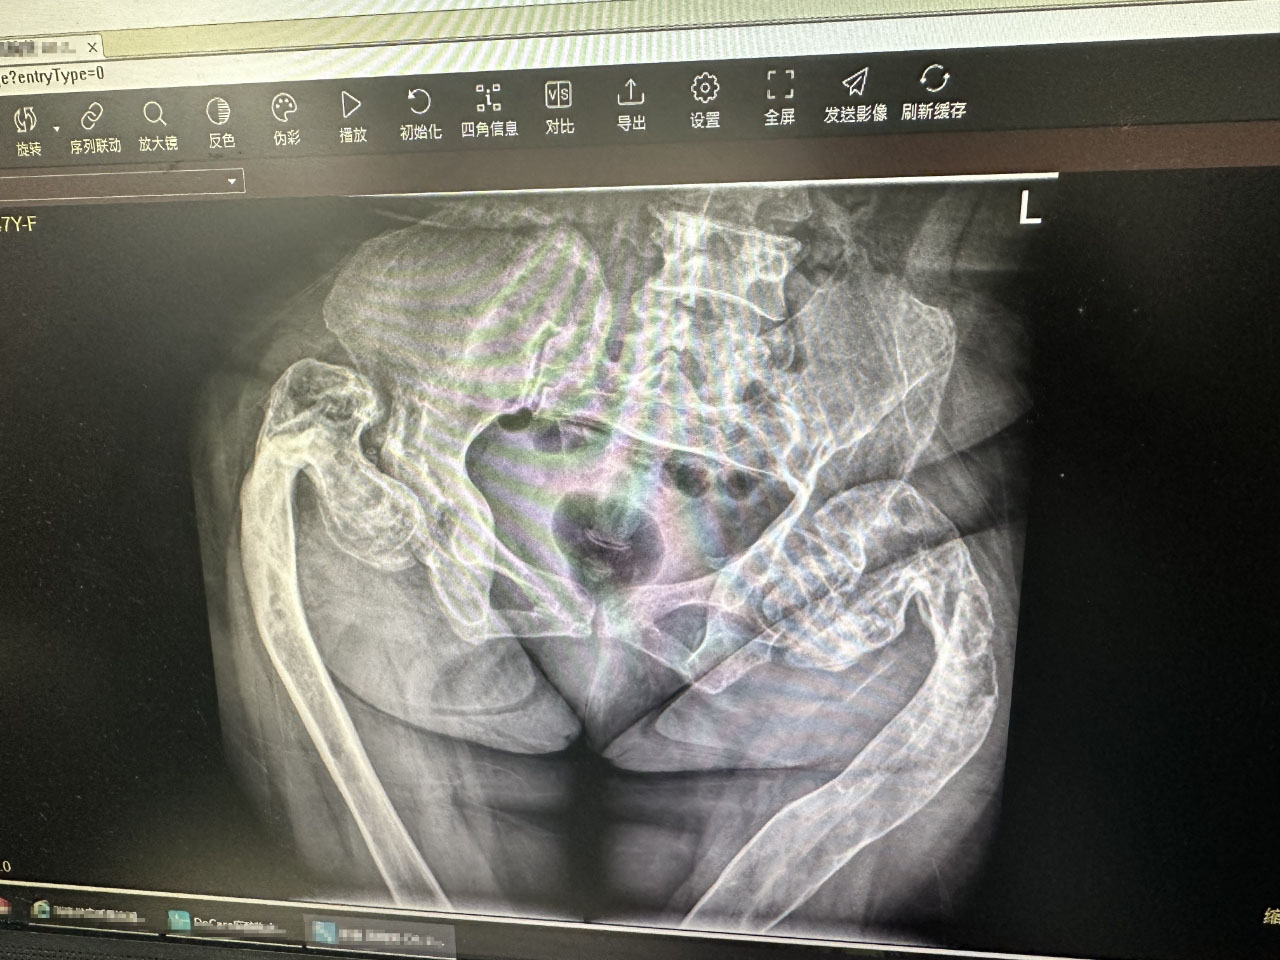

On April 10, Prof. Freude and Director LIANG first conducted ward round in the morning for the patient who was to undergo surgery on the following day. The patient suffered from an unknown genetic or gene mutation disorder, giving rise to severe deformity of her lower limbs, poor bone quality due to osteofibrous dysplasia, and needed to be operated on for fracture on the proximal femur.

圖片關(guān)鍵詞

After assessing the patient's underlying disease, along with a physical examination on her genetic history, Prof. Freude proposed to fixate the fracture with elastic nails to help the patient to reduce the pain and hopefully achieve bone healing.